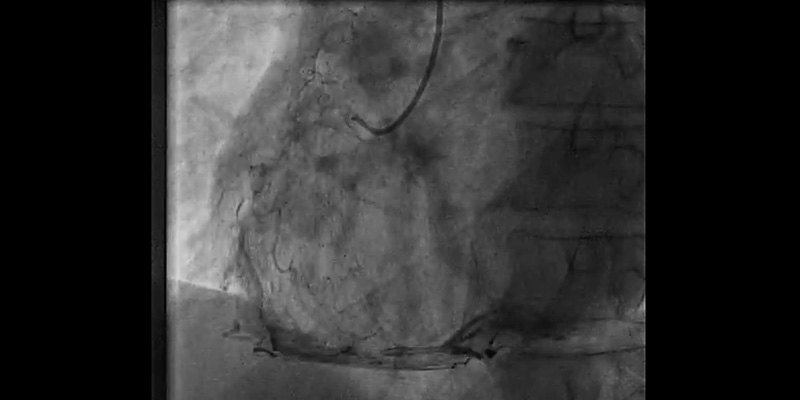

Coronary Angiography

• Right coronary artery showed significant stenosis in the proximal segment (70%), severe calcification of the proximal and mid segments, and critical stenosis in the distal segment (95%)

• LAD with stent in the proximal segment without restenosis. Mid LAD showed severe calcification with a significant stenosis - 85% (Medina 1-0-1) involving the diagonal ostium

• Circumflex artery: first obtuse marginal, 70% stenosis. Second obtuse marginal with implanted stent, without restenosis

Syntax score I: 20, Syntax score II PCI: 28.2, CABG 30.5.